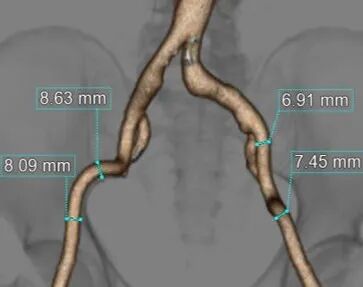

测量数据:

斑马导丝是治疗什么的「胸有乾坤」至简至易 行之有效—— Zone 0 TBE植入治疗弓部动脉瘤病例报道_https://www.jmylbn.com_新闻资讯_第8张

近端锚定区直径

斑马导丝是治疗什么的「胸有乾坤」至简至易 行之有效—— Zone 0 TBE植入治疗弓部动脉瘤病例报道_https://www.jmylbn.com_新闻资讯_第9张

无名动脉直径

斑马导丝是治疗什么的「胸有乾坤」至简至易 行之有效—— Zone 0 TBE植入治疗弓部动脉瘤病例报道_https://www.jmylbn.com_新闻资讯_第10张

远端锚定区直径.

斑马导丝是治疗什么的「胸有乾坤」至简至易 行之有效—— Zone 0 TBE植入治疗弓部动脉瘤病例报道_https://www.jmylbn.com_新闻资讯_第11张

双侧入路直径